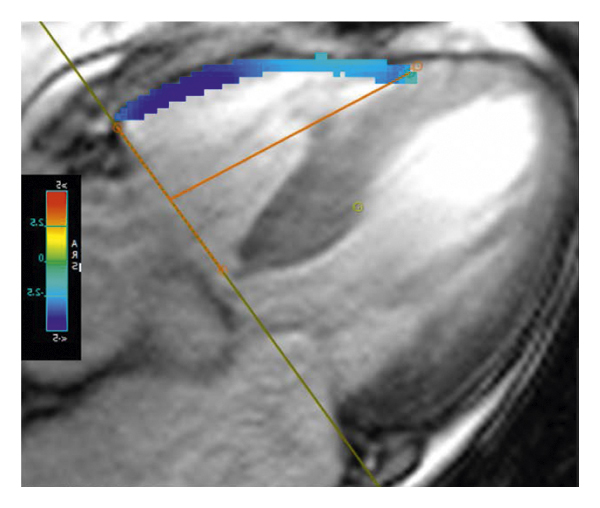

2.3. 이미징 분석모든 이미지 분석은 시중에서 판매되는 소프트웨어(cvi42, Circle Cardiovasic Imaging, Inc. Calgary, Canada)를 사용하여 수행되었습니다. 심장 기능을 측정하기 위해 심장내막 및 심외막 추적을 확장기 말기 및 수축기 말기의 직렬 단축 슬라이스에서 수동으로 수행했습니다. LV/RV 확장기말 용량(EDV), 수축기말 용량(ESV) 및 LV/RV 박출률을 포함한 전체 LV/RV 수축기 기능이 계산되었습니다. LV 및 RV 심근 스트레인 분석은 장축 4챔버 및 단축 슬라이스를 조직 추적 모듈에 로드하여 수행되었습니다(그림 1 (a) 및 1 (b)). RVT는 중실의 3회 측정하였고, 평균 두께를 계산하였다(도 1 (c) 및 1 (d)). GRPS(글로벌 라디칼 피크 변형), GLPS(글로벌 세로 피크 변형) 및 GCPS(글로벌 원주 피크 얼룩)를 포함하여 전역 특징 추적 매개변수가 자동으로 획득되었습니다. 최고 수축기 변형률(PSSR, 이완기부터 다음 수축기까지의 모든 단계에 대한 절대값의 최대 변형률)과 최고 확장기 변형률(PDSR, 수축기부터 다음 수축기까지 모든 단계에 대한 절대값의 최대 변형률)은 다음과 같습니다. 또한 분석했다. 양수 기호와 음수 기호는 서로 다른 동작 방향을 나타냅니다. 앞서 기술한 바와 같이[ 16 ], 정상적인 RVT 값은 7mm 이하로 정의되었다. 기준에 따라 CA 및 HCM 환자를 RV 비대(RVT >7 mm) 또는 RV 비대(RVT ≥7 mm) 환자에 따라 하위 그룹으로 나누었습니다.

(ㅏ) -